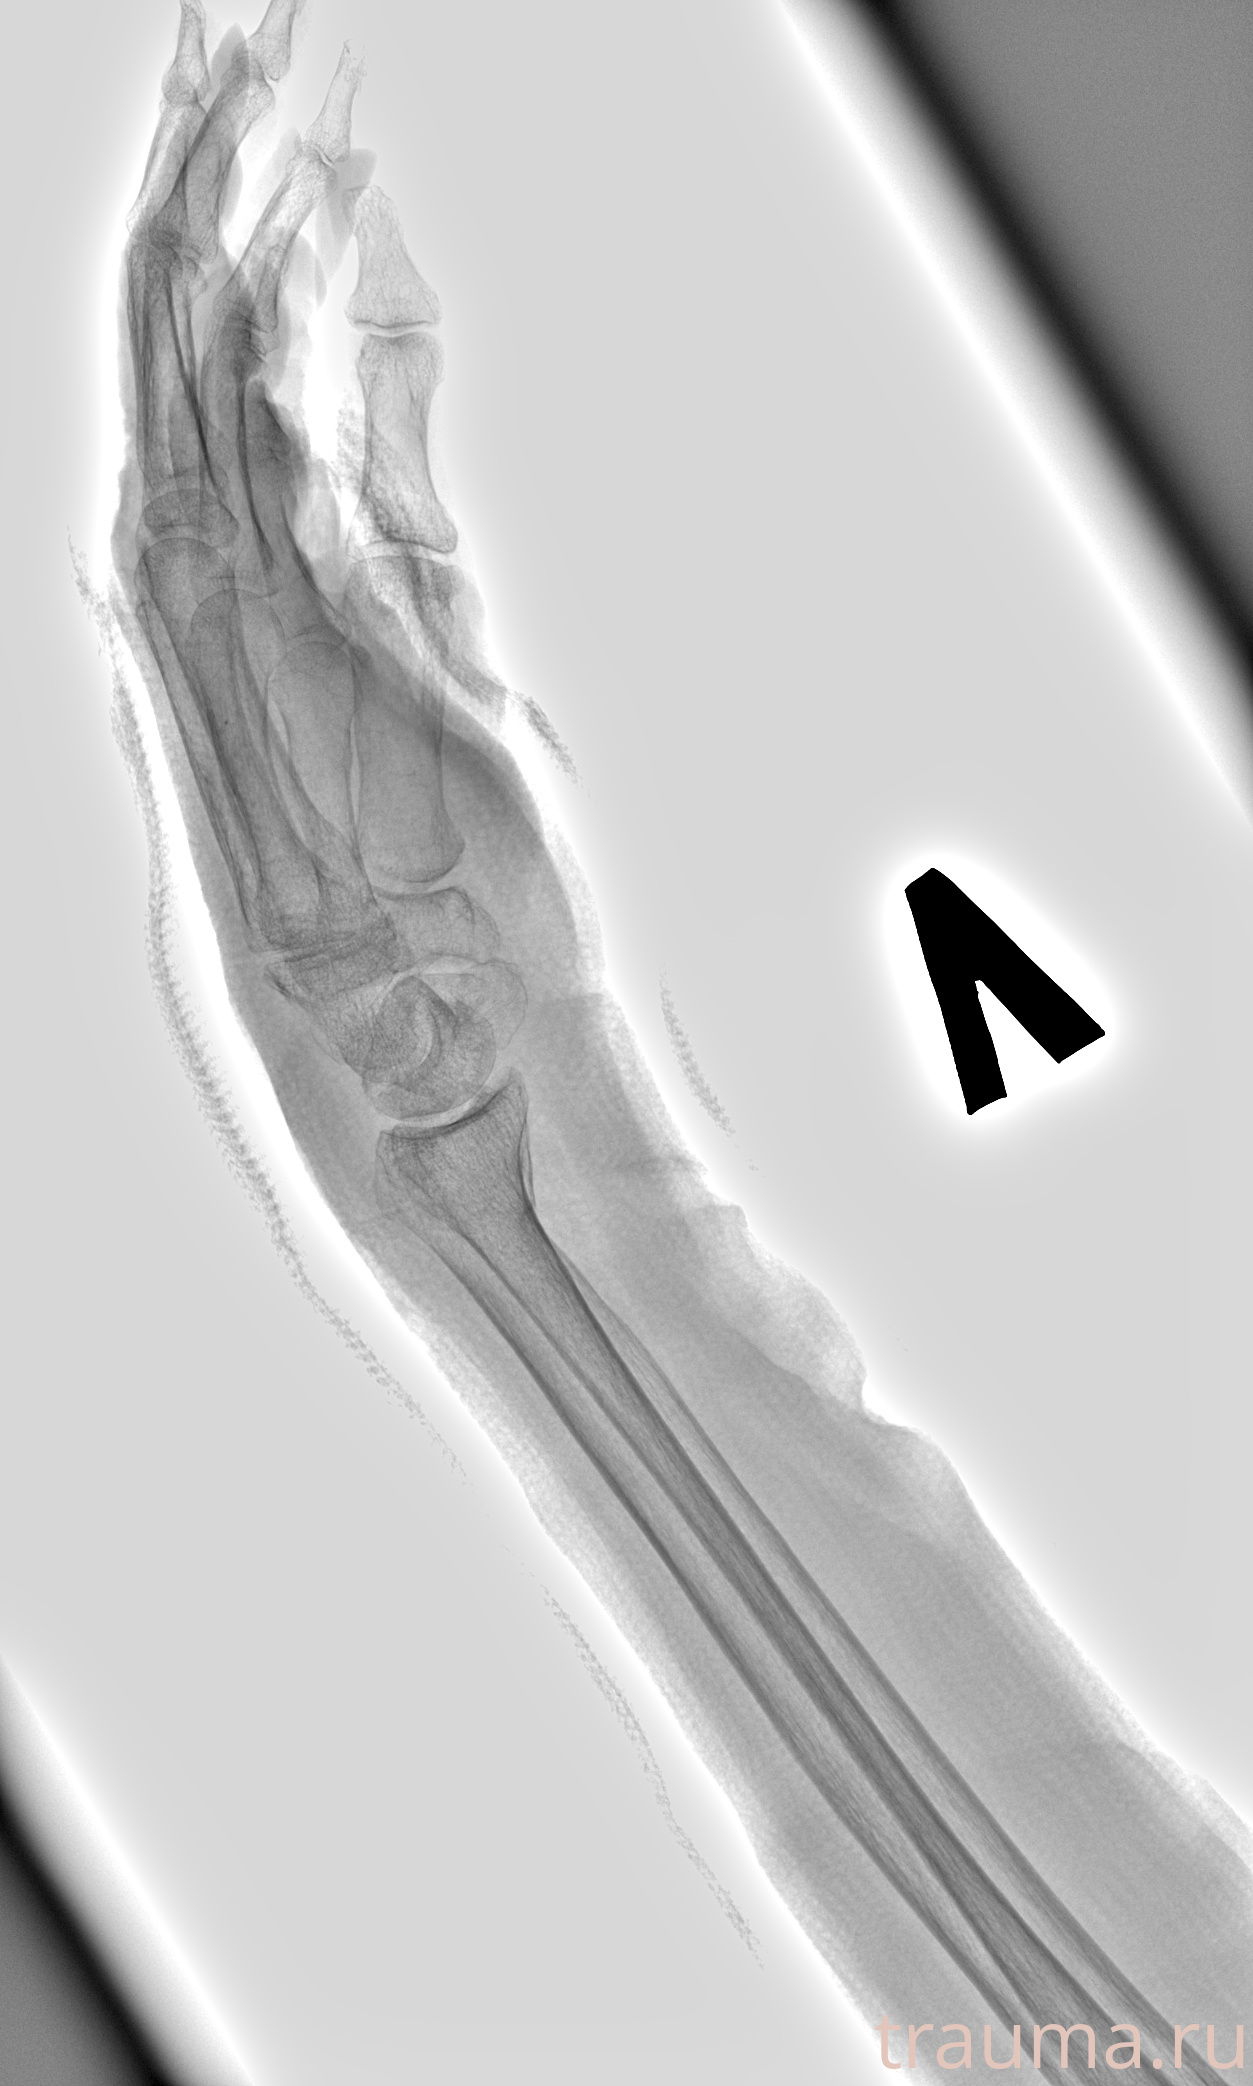

Рентген на дому: по вашему адресу приезжает врач-рентгенолог, травматолог-ортопед с мобильным рентгеновским аппаратом, проводит диагностику травмы или заболевания, делает необходимые рентгенограммы, дает рекомендации по дальнейшему лечению. Получить качественные снимки в домашних условиях возможно благодаря уникальной методике, разработанной МосРентген Центром для института  Склифосовского